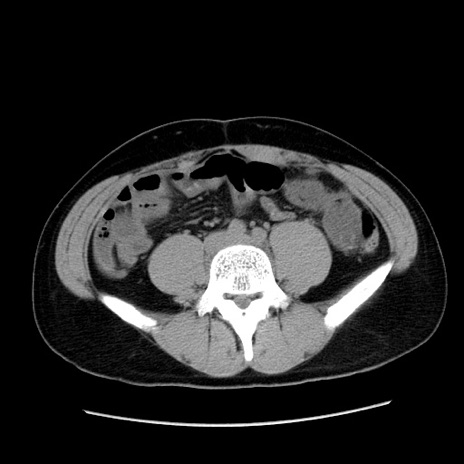

症例36(横断像)

【症例】20歳代 男性

【主訴】心窩部痛

【現病歴】今朝より上腹部痛あり。一旦軽快していたが再度出現したため救急要請。昨日夕に白身の魚を含む刺身を食べた。

【身体所見】BP 136/89mmHg、HR 74/min、BT 37.0℃、腹部:膨満、軟、心窩部に圧痛あり。反跳痛なし、筋性防御なし、腸雑音やや亢進あり。

【データ】WBC 17700、CRP 0.48